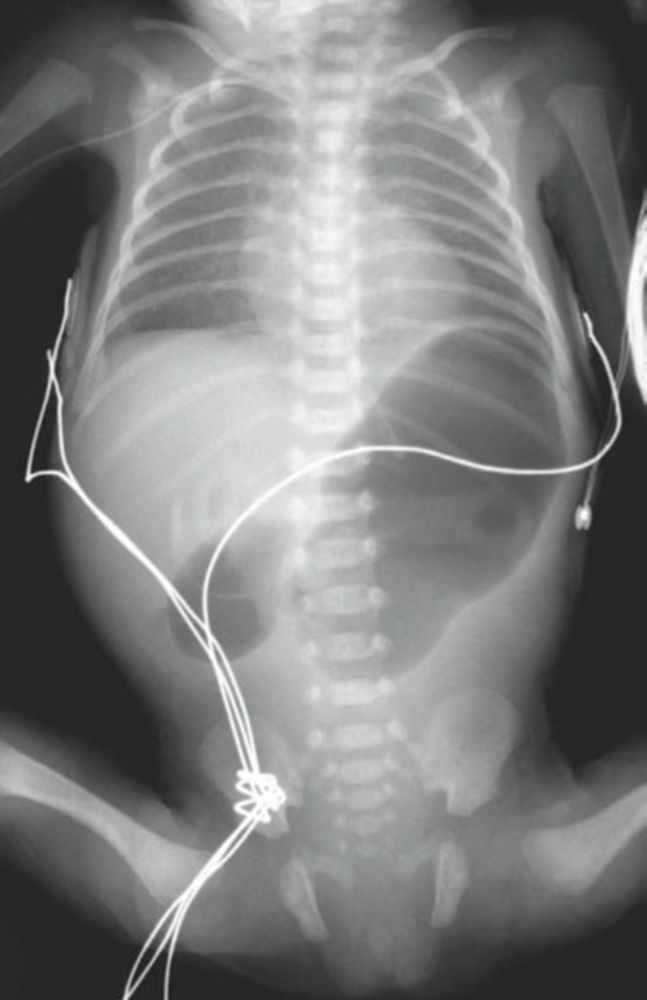

Infant with Nonbilious Vomiting and Lack of Stools Post category:Spot Diagnosis Post published:June 11, 2022 Share on Facebook Share on X (Twitter) Share on Pinterest Share on Email Share on Reddit Infant with Nonbilious Vomiting and Lack of Stools What is the diagnosis in this infant with ongoing episodes of nonbilious vomiting and a lack of stools since birth? CLICK FOR FULL CASE AND ANSWER Share on Facebook Share on X (Twitter) Share on Pinterest Share on Email Share on Reddit Read more articles Previous Post3-year-old Girl with Pruritic Blanching Rash Next Post2-year history of a nonhealing ulceration on the left heel You Might Also Like Patient with Postprandial Dyspnea, Epigastric Pain and Substernal Fullness May 29, 2022 Necrotic Skin Lesions on Nose, Ears, and Legs after Exposure to Cold January 15, 2022 Punctate Opacities Along the Entire Colon on X-Ray September 11, 2021